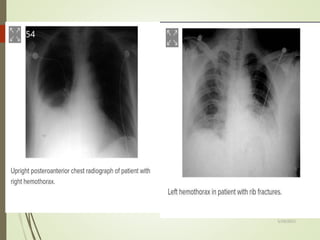

HEMOTHORAX

 Hemothorax is the accumulation of blood in the intrapleural

spaces.

 Bleeding is usually from intercostal artery in lacerated chest

wall or from underlying contused lung, heart or great vessel.

 Massive hemothorax is bleeding of more than 1500ml into

pleural cavity

 Hemothorax can be associated with a single rib fracture.